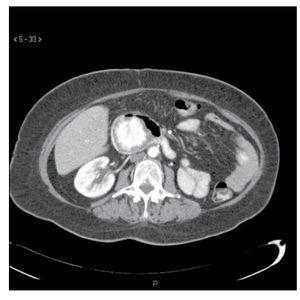

El informe histopatológico de la pieza quirúrgica reveló una masa metastásica de 4.9 cm por 4 cm en la segunda porción del duodeno, a 2 cm del ámpula de Vater, con márgenes quirúrgicos negativos y sin involucro linfático. En la imagen microscópica se observaron células tumorales con un núcleo pequeño, citoplasma claro y con nucléolos prominentes, lo que corresponde a un grado nuclear I (Figura 3). El tumor se encontraba organizado en un patrón acinar, mostrando espacios luminales centrales llenos de eritrocitos.

¿ Figura 3. Tumor metastásico organizado en un patrón acinar, mostrando espacios luminales centrales llenos de eritrocitos A). Células tumorales con núcleo y nucléolo pequeño B).